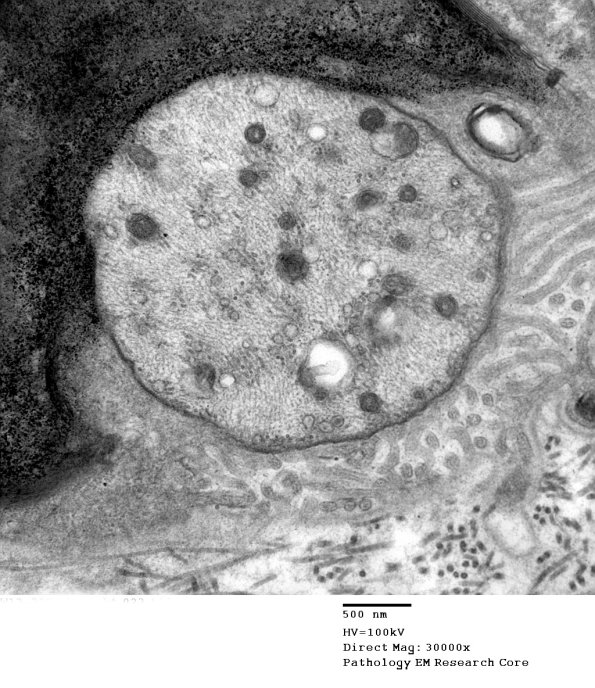

Higher magnification of image #7A1. (electron micrograph)